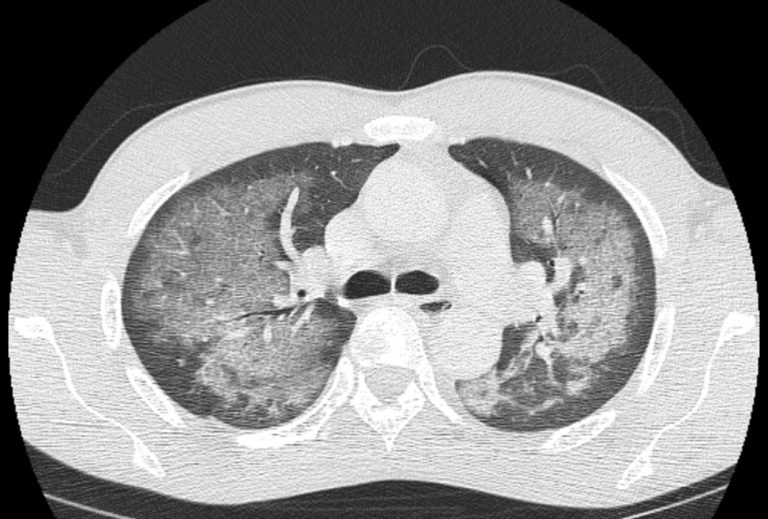

Emergency Medicine EducationEM3AM Crack Lung emDOCs What Causes Chest To Crack if you are experiencing chest pain or a “popping” sternum—a clicking or cracking sensation when moving or breathing deeply—then you may be suffering from costochondritis. If so, you might wonder. a viral or bacterial lung infection, autoimmune disease, or other conditions in the lungs or chest can cause. the causes of crepitus in the lungs usually involve. What Causes Chest To Crack.